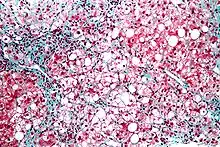

| Micrograph showing a fatty liver (macrovesicular steatosis), as seen in non-alcoholic fatty liver disease. Trichrome stain. | |

Pathology

The fatty change represents the intracytoplasmatic accumulation of triglycerides (neutral fats). At the beginning, the hepatocytes present small fat vacuoles (liposomes) around the nucleus (microvesicular fatty change). In this stage, liver cells are filled with multiple fat droplets that do not displace the centrally located nucleus. In the late stages, the size of the vacuoles increases, pushing the nucleus to the periphery of the cell, giving a characteristic signet ring appearance (macrovesicular fatty change). These vesicles are well-delineated and optically "empty" because fats dissolve during tissue processing. Large vacuoles may coalesce and produce fatty cysts, which are irreversible lesions. Macrovesicular steatosis is the most common form and is typically associated with alcohol, diabetes, obesity, and corticosteroids. Acute fatty liver of pregnancy and Reye's syndrome are examples of severe liver disease caused by microvesicular fatty change.[19] The diagnosis of steatosis is made when fat in the liver exceeds 5–10% by weight.[13][20][21]

Severe fatty liver is sometimes accompanied by inflammation, a situation referred to as steatohepatitis. Progression to alcoholic steatohepatitis (ASH) or non-alcoholic steatohepatitis (NASH) depends on the persistence or severity of the inciting cause. Pathological lesions in both conditions are similar. However, the extent of inflammatory response varies widely and does not always correlate with degree of fat accumulation. Steatosis (retention of lipid) and onset of steatohepatitis may represent successive stages in FLD progression.[23]

Liver disease with extensive inflammation and a high degree of steatosis often progresses to more severe forms of the disease.[24] Hepatocyte ballooning and necrosis of varying degrees are often present at this stage. Liver cell death and inflammatory responses lead to the activation of hepatic stellate cells, which play a pivotal role in hepatic fibrosis. The extent of fibrosis varies widely. Perisinusoidal fibrosis is most common, especially in adults, and predominates in zone 3 around the terminal hepatic veins.[25]